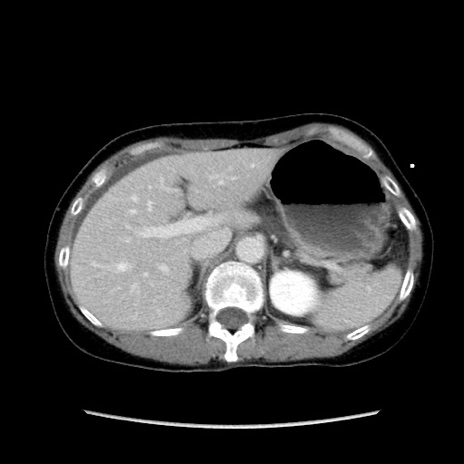

症例32(横断像)

【症例】40歳代 女性

【主訴】上腹部痛、嘔気・嘔吐

【現病歴】約9時間前頃から急に上腹部痛、嘔気、嘔吐が出現。改善しないため救急要請。

【既往歴】子宮頚癌(広汎子宮全摘術、放射線療法)、腸閉塞

【身体所見】腹部:平坦、軟、腸雑音亢進、上腹部を中心に腹部全体に圧痛あり。

【データ】WBC 8400、CRP 0.03